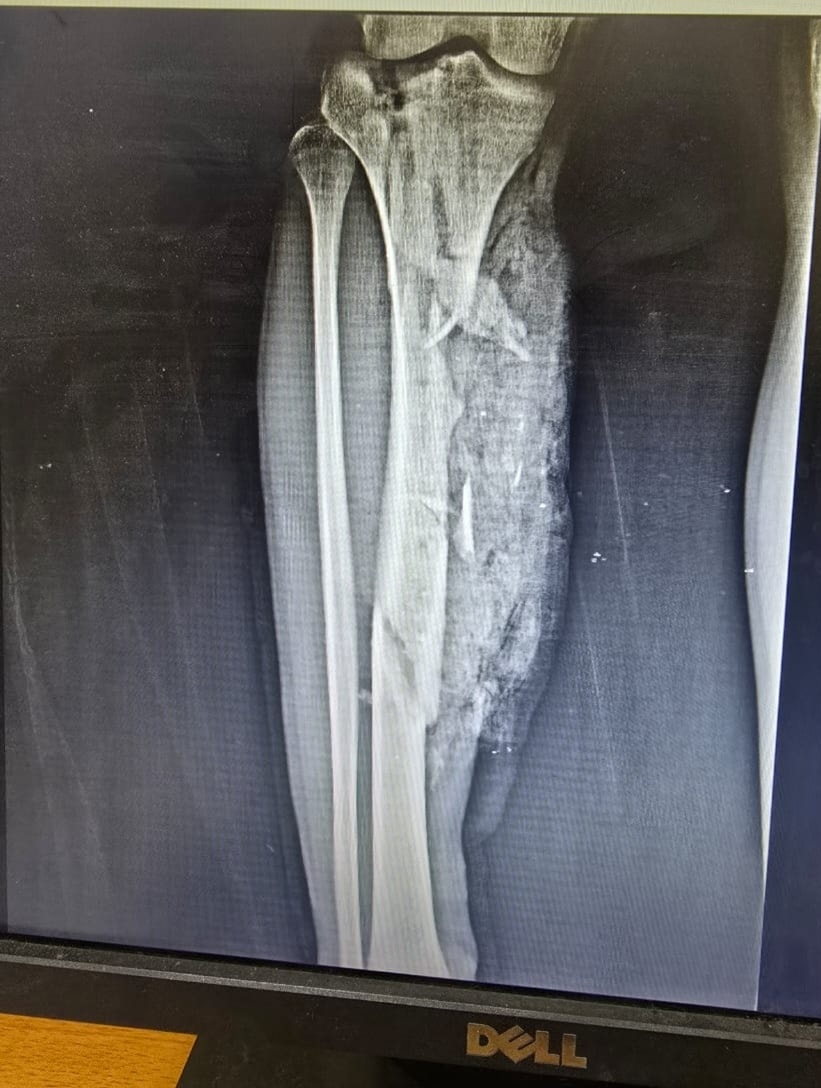

الأشعة الخاصة بالمريض

وتابعت المستشفى، أنه تم تجهيز المريض ولياقته من قسم التخدير وتحضيره وتجهيز الدم والبلازما اللازمة للحالة، حيث استقر التشخيص علي كسر متفتت مفتوح مع فقد جزء من العظام بالعضد الأيمن مع قطع بالعضلات، وكسر متفتت مفتوح مع فقد جزء من العظام بالساق الأيمن مع قطع بالعضلات، وتهتك بالقدم اليمنى وقطع بالأوتار والعضلات، مع كسر بعظام القدم.

وأشارت، إلى أنه بدأت العملية قبل سطوع الشمس ليأتي يوم جديد ببارقة أمل وحياة تولد من جديد بفضل الله ورعايته، وتم عمل توصيل الأوتار والعضلات المتهتكة وتثبيت الكسور باستخدام مثبتات خارجية مع مسامير مجوفة وأسلاك معدنية، وسط تهديد واضح ببتر الساق لسوء حالة الجرح، ولكن جهود الفريق الطبي كان لهم رأي آخر واستطاعوا أن يعبروا بالشاب لبر الأمان.